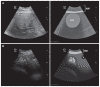

The purpose of this study was to develop a method for identification of the pylorus, in lactating Holstein cows, based on ultrasound examination and the use of external anatomical landmarks such as the mammary vein (anulus venae subcutaneae abdominis). An ultrasound method based on successive identification of 4 internal anatomical landmarks was developed. The procedure was performed 157 times, on clinically healthy lactating Holstein cows, with a portable ultrasound machine equipped with a 3.5 MHz curvilinear probe. The pylorus was identified with a success rate of 98.7% (155 times out of 157 procedures). The average position of the pylorus was noted near the entrance of the right mammary vein, with a craniocaudal and dorsoventral dispersion. This ultrasound method of identifying the pylorus is simple, effective, and rapid.